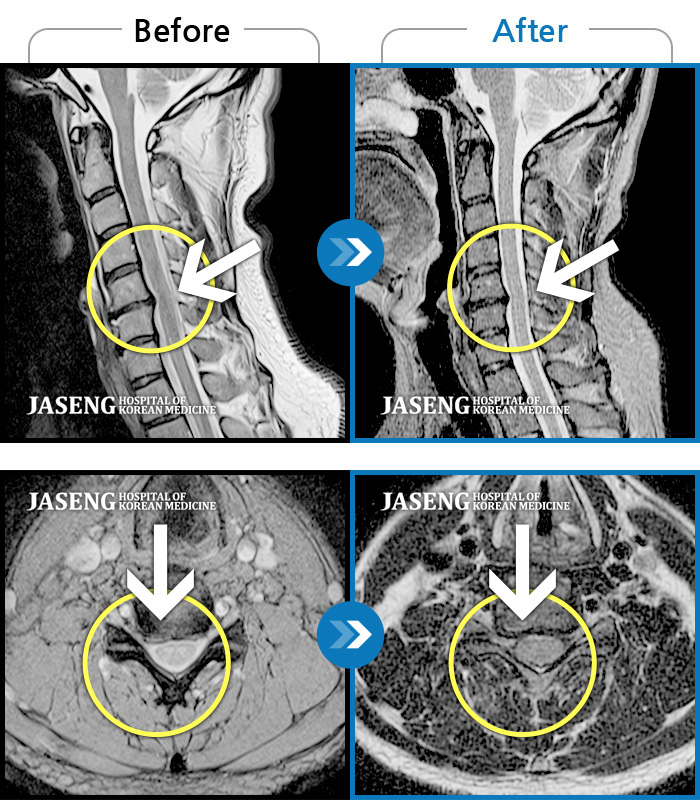

목디스크

도움받은 사례

인천 · 강아현 원장

좌측 목 통증 및 견갑내연 통증, 팔 전체 통증으로 일상생활에 어려움을 겪는 상태로 내원하셨습니다.

촬영시기

2023.11.27 ~ 2024.05.27

2024.06.03

조회수 481